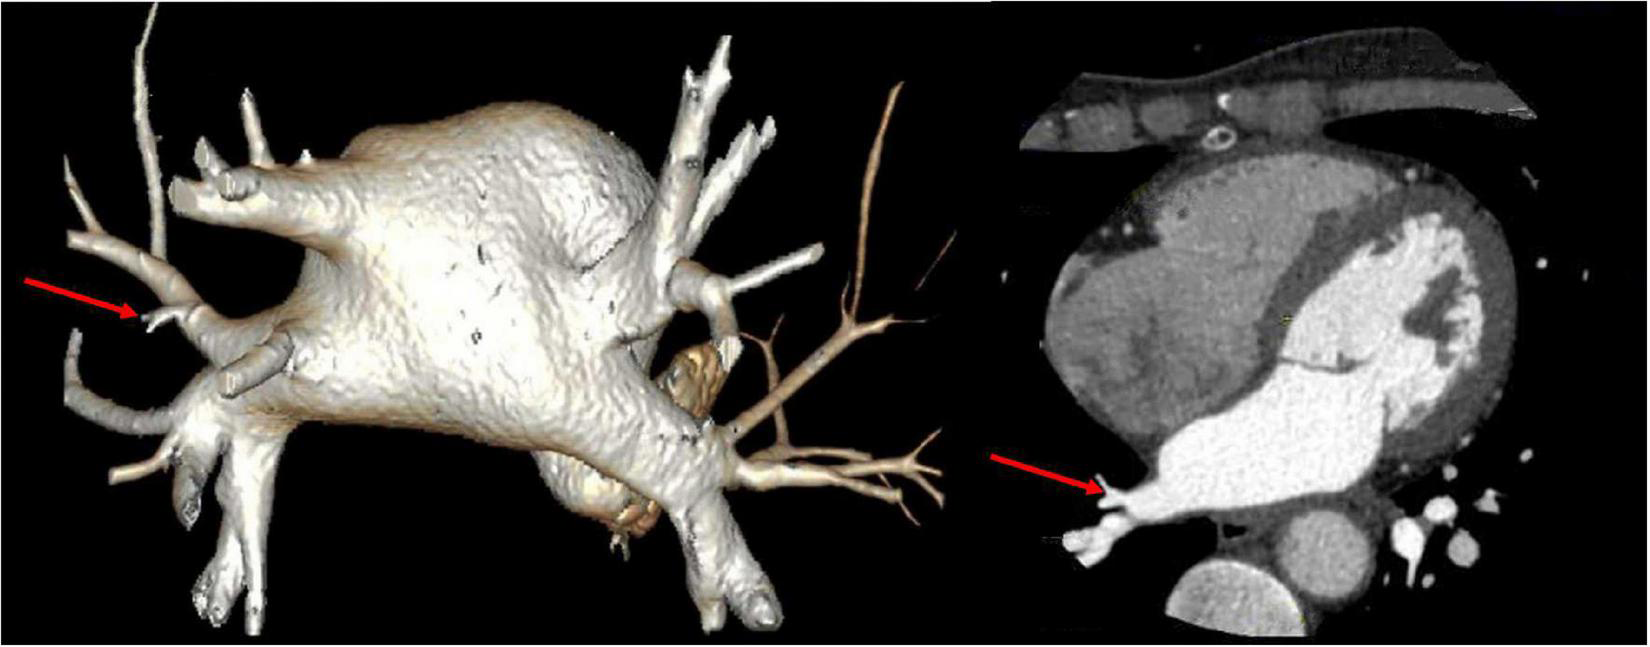

Vital signs were monitored within 24 h after admission; the patient got external auditory canal bleeding 3 h after thrombolysis. The further investigation and inquiry on her medical history showed a history of ear trauma 1 week before. Bleeding was stopped via external auditory canal tamponage. The cranial MRI and systemic vascular examination were arranged to find the cause of stroke, no abnormal signal was found in T1-weighted imaging, T1WI (T1), T2-weighted imaging, T2WI (T2), and diffusion-weighted imaging (DWI), and there was no microhemorrhage-related signal in susceptibility weighted imaging (SWI) (Figure 2). In the magnetic resonance angiography (MRA) measurement, intracranial vessels were indicated normal and bilateral embryonic posterior cerebral arteries were observed. Carotid ultrasound showed bilateral carotid intima thickening with plaque formation and plaque was found in the right subclavian artery. Arteriovenous ultrasound of lower extremity showed normal. Transcranial Doppler showed a rapid increase in the flow rate of the left middle cerebral artery, and 5–6 microembolic could be found in foaming experiment, supporting a direct pathway from pulmonary circulation to the systemic circulation (RLS). Cardiac systemic examination was completed: 24-h Holter showed sinus bradycardia, short atrial tachycardia, and atrial premature beats (some of which were not transmitted). Widening ascending aorta was shown on echocardiography. Thrombus was not found in bilateral atrium and left auricle in transesophageal echocardiography, also no septal shunt beam was observed in the atrial septal fossa ovale. From the data that were collected from the other hospital, left atrium was slightly larger and the middle branch of the right pulmonary vein was mutated on the CT angiography (CTA) of the left atria and pulmonary veins on 26th September (Figure 3). Diagnosis of transient ischemic attack, cardiogenic cerebral embolism, paroxysmal atrial fibrillation, pulmonary arteriovenous fistula, hypertension with Grade 2, and hyperlipidemia were observed after admission. She was suggested to restart the anticoagulant treatment deal to the CHA2DS2-VAS score was 4 and HAS-BLED score was 2. The pulmonary artery digital subtraction angiography (DSA) was also suggested after patients were discharged.

FIGURE 3

CT angiography (CTA) of left atria-pulmonary vein showed the middle branch of the right pulmonary vein was variable.